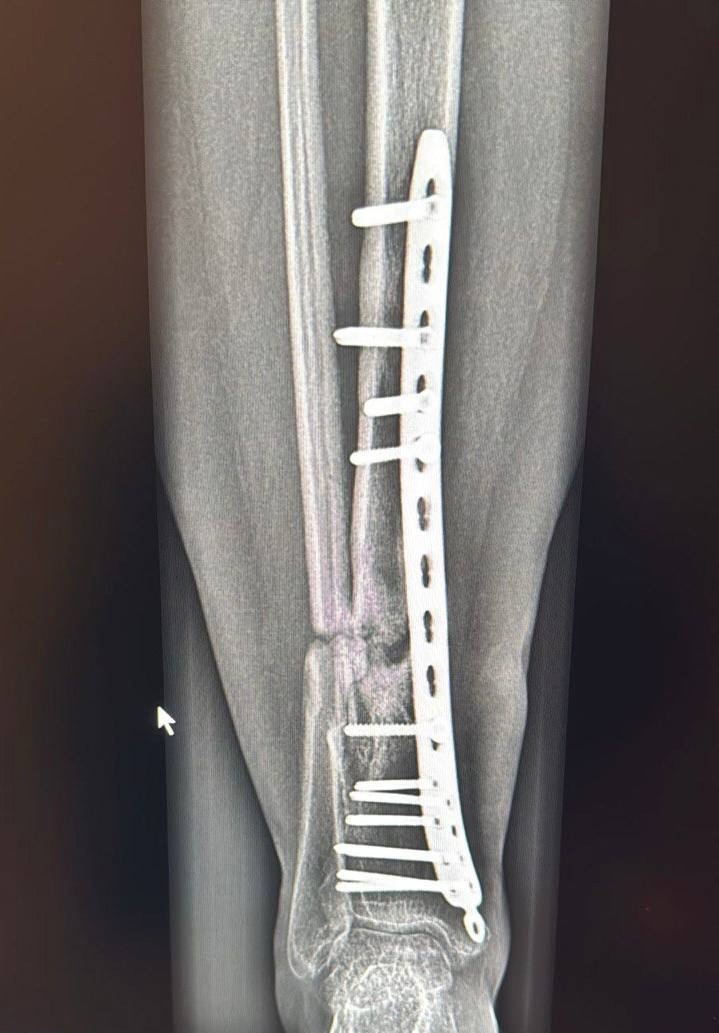

«Сначала мы разобрали кости, которые срослись неправильно. Там была костная мозоль, сформировался ложный сустав, на который нельзя опереться. Пришлось все это разделять, убирать рубцовые измененные ткани, зачищать, накладывать пластину, выполнять костную пластику специальными искусственными трансплантатами», — рассказал ортопед Владимир Росторгуев.

Операция продлилась 4,5 часа. Хирурги также собрали кости на титановую пластину и закрепили на 14 болтов.

Процесс восстановления после операции идет хорошо: женщина перестала чувствовать боль в ноге, которая её беспокоила больше года. По результатам контрольного рентгеновского снимка кость начала срастаться, признаков смещения металлоконструкции нет. Специалисты разрешили пациентке заменить ходунки на палочку, чтобы разрабатывать ногу. Вскоре она сможет ходить самостоятельно.